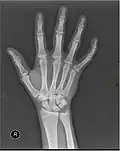

X-ray

X-ray image of right hand with thumb on left. -